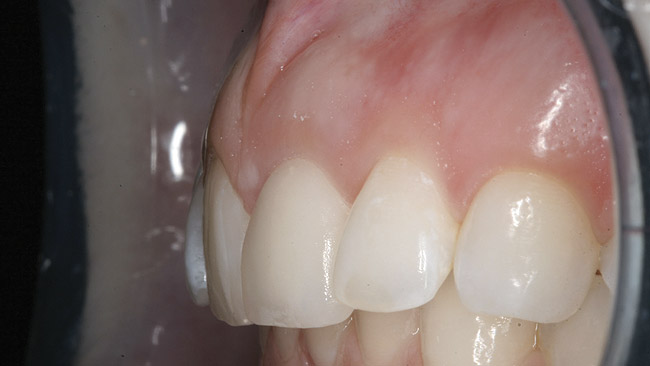

Figure 11  Original feldspathic porcelain crown placed by restorative dentist, tooth No. 9—facial view.

Figure 11

Figure 12  Localized moderate gingival inflammation on facial aspect of No. 9 (2 years post-cementation).

Figure 12

Two years later, however, the patient returned to her restorative dentist’s office complaining that “something felt different” on tooth No. 9. Localized moderate gingival inflammation was present on the facial aspect of No. 9 (Figure 12). A straight facial probing depth of 6 mm and severe bleeding on probing were also evident facially, suggesting a vertical root fracture.